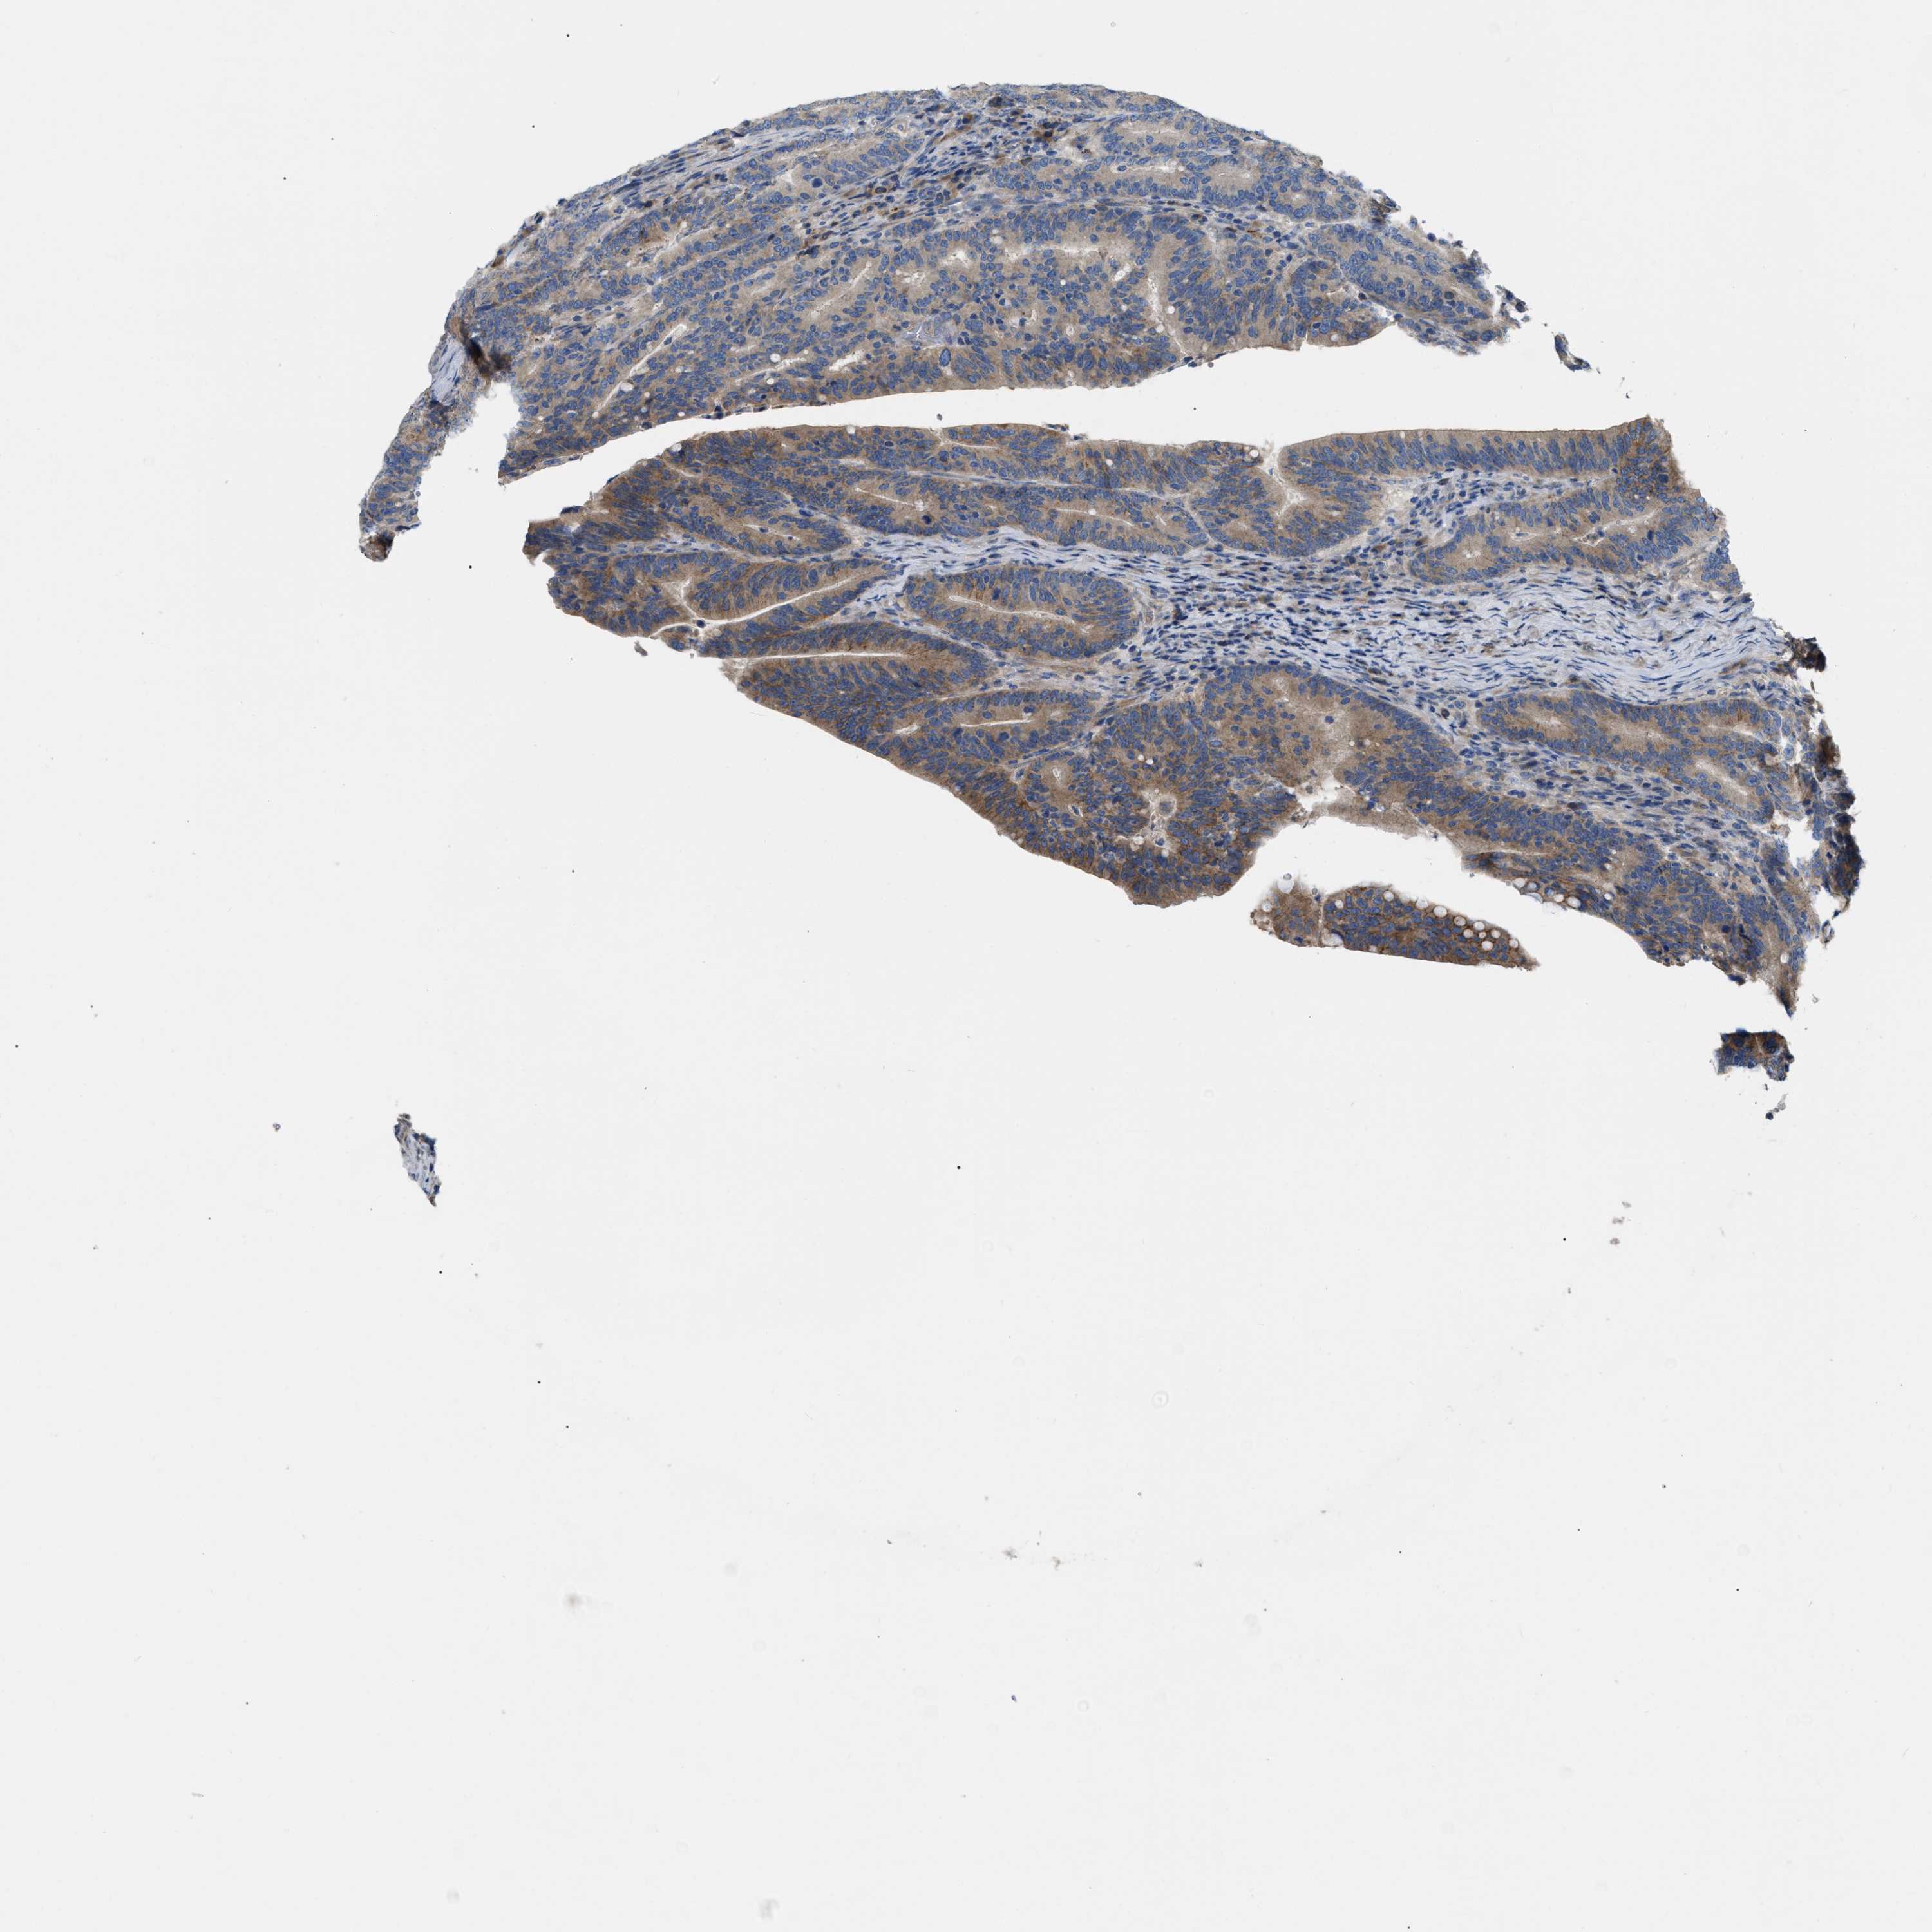

CANCER COLORECTAL CANCER Show tissue menu

Colorectal cancer

Rectum adenocarcinoma